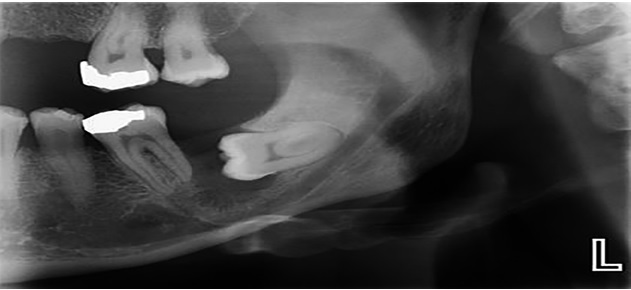

Sâu răng và tổn thương răng số 7: Do vị trí răng khôn nằm sâu trong cung hàm, việc vệ sinh thường gặp nhiều khó khăn. Khi răng khôn mọc lệch về phía trước, chúng có thể tạo khe hở với răng số 7, khiến thức ăn dễ mắc lại và khó làm sạch. Lâu ngày, vi khuẩn phát triển trong vùng này có thể gây sâu răng khôn, sâu răng số 7 hoặc viêm tủy răng, làm ảnh hưởng đến chức năng ăn nhai và có thể phải điều trị phức tạp hơn.

.jpg)

Hình ảnh răng khôn mọc lệch gây sâu răng số 7